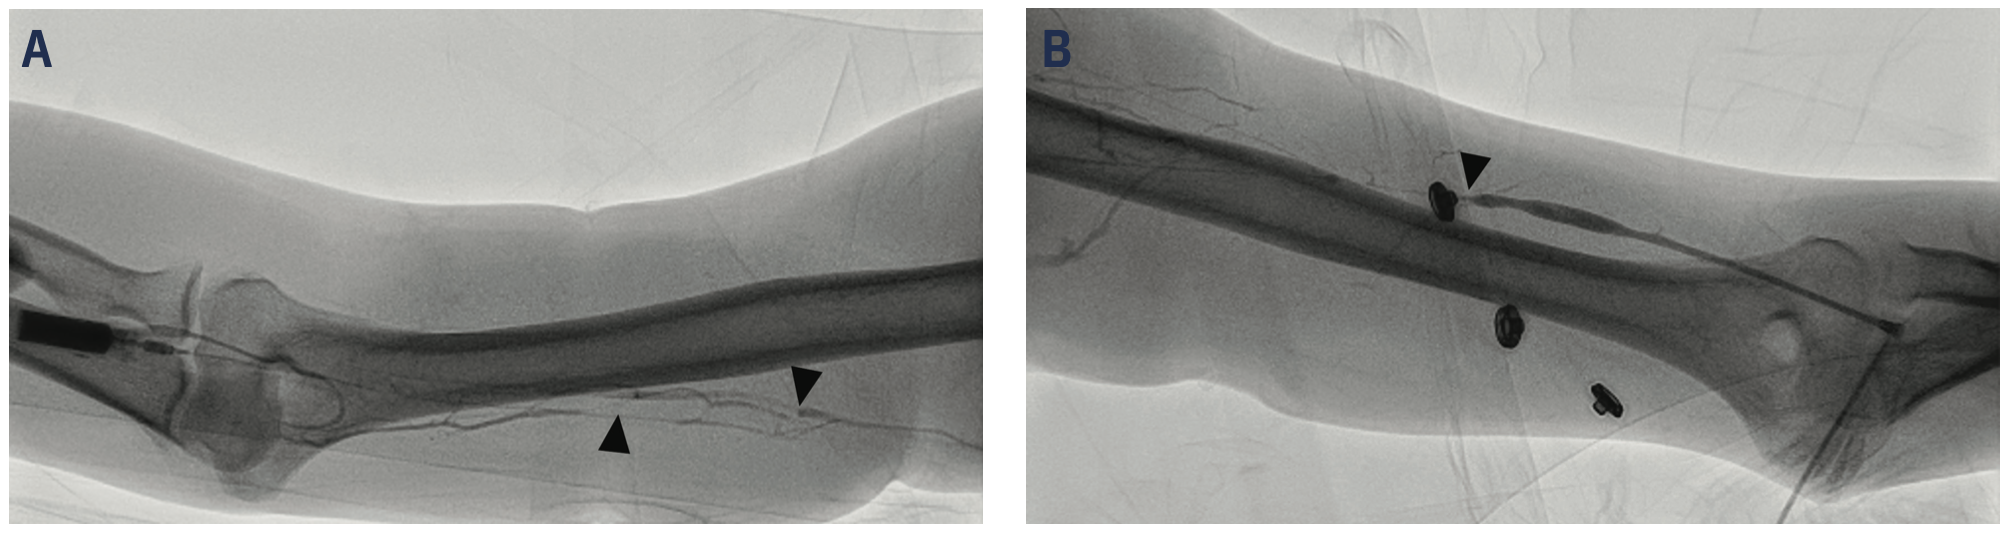

On the day of procedure, the patient had no chest pain. He was on his chronic home requirement of 4 liters of oxygen. Physical exam revealed bibasilar dry crackles, no pericardial rub, no peripheral edema, and no elevation of jugular venous pressure. A RHC was performed with ultrasound-guided right brachial venous access. Despite successful entry into an ultrasound-documented brachial vein, the guidewire could not be advanced >10 cm without meeting resistance. Several similar attempts with adjacent veins also failed. Proximal vein images show diffuse and severe narrowing of the right brachial medial veins (Figure 4A) and were assumed to be a consequence of prior PICC placement. Left brachial vein access was then attempted and was also noted to be difficult due to severe venous narrowing (Figure 4B), but access was eventually achieved via the cephalic vein using the assistance of an angioplasty guidewire. The 5 French (F) balloon-tipped catheter was advanced to the subclavian vein also with some difficulty, requiring a guidewire to facilitate passage, and angiography showed a large axillary vein on injection of contrast into the brachial vein. Both the internal jugular vein and superior vena cava (SVC) were extremely large in caliber with turbulent angiographic flow. Further advancement of the balloon catheter required an .014-inch guidewire (Figure 5A-B). The guidewire preferentially moved into sites one would expect of the azygous and internal thoracic veins. Finally, after traversing the complex subclavian vein, hemodynamic measurements were obtained with the 5F balloon-tipped catheter. Blood oxygen saturations with hemodynamic recordings showed right heart hemodynamics and cardiac output that were normal (Table 1). There was an inability to advance the balloon catheter safely to the pulmonary capillary wedge pressure position, despite using a guidewire, due to strong proximal resistance, so this measurement was deferred. After collecting sufficient hemodynamic data to determine transplant candidacy, the 5F catheter and sheath were removed. Hemostasis was obtained using manual compression. There were no postprocedural complications.